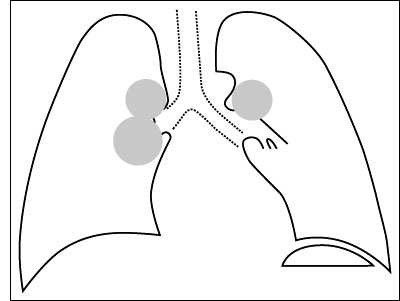

Esquema 26 Comentario placa 26 En el hilio derecho se observa dos masas redondeadas y en el hilio izquierdo es clara la existencia de otra en la parte superior con otra dudosa más abajo. Lo más probable es que se trate de adenopatías hiliares bilaterales, pero es necesaria la placa lateral para establecer su situación con precisión. Examine la placa lateral 27 y ubique las masas. |